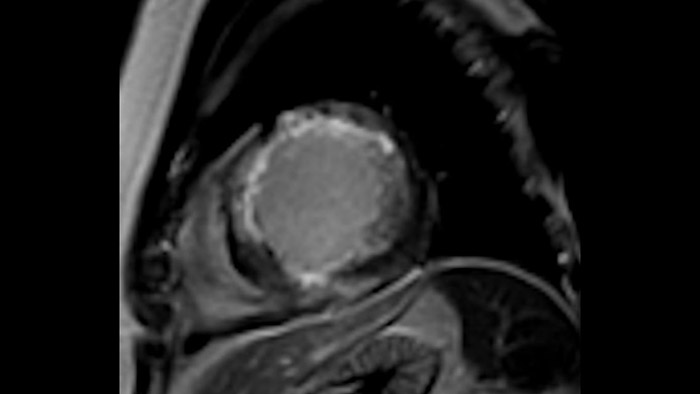

Diagnostic and prognostic utility of cardiac MR is increasing. Assess the anatomy and function of the heart using cine acquisitions, acquire information about perfusion and viability of the cardiac tissue, visualise potential edema with black blood sequence, access and even quantify tissue characterisation with CardiacQuant.

IntelliSpace Portal MR Caas5,6 Strain7 assists in patient diagnosis and monitoring by providing global strain parameters such as global longitudinal strain (GLS), global circumferential strain (GCS), and global radial strain (GRS), using short and long axis MR images, as well as describing the myocardium deformation- such as shortening, thickening, and lengthening during the cardiac cycle.